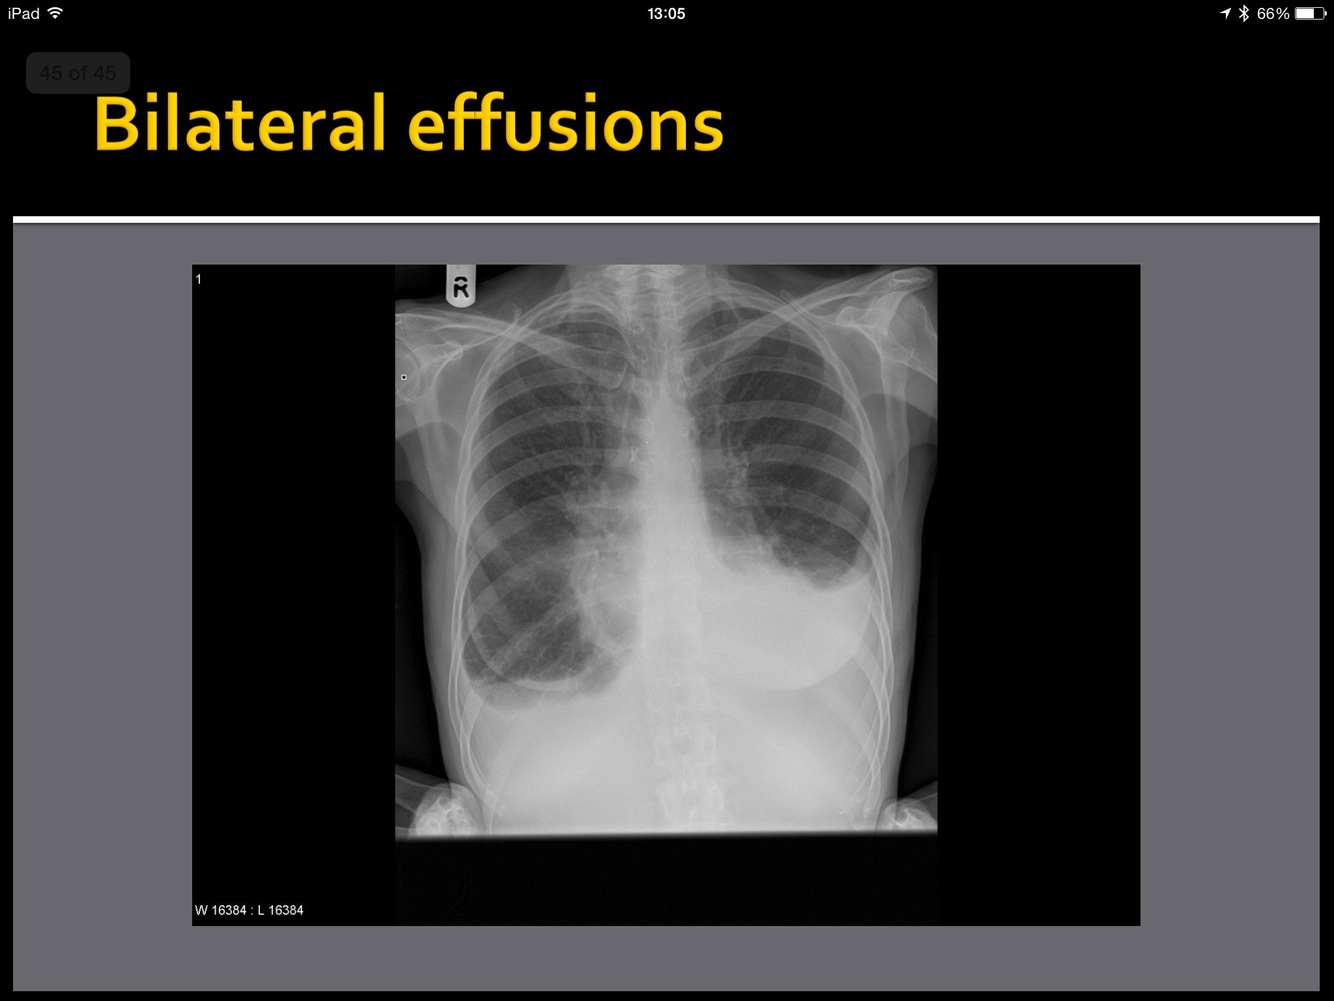

Point to them!

whatis the abnormality?